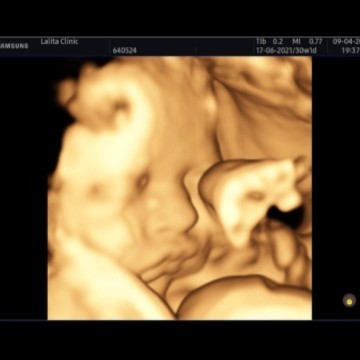

ภาพซาวด์4มิติ

ขอดูภาพซาวด์4มิติ ของแม่ๆท่านอื่นหน่อยคะ บ้านนี้ซาวด์ปัยน้องยิ้มเล่นไปด้วย ให้ทายว่าน้องเปนผญ.หรือผช.😊